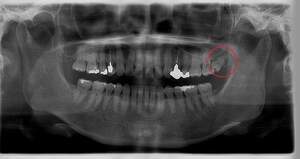

右下奥歯が痛い症例

- 抜歯前写真(レントゲン)

| 年齢 | 40代・男性 |

|---|---|

| 主訴 | 右下奥歯が痛い |

| 親知らずの生え方 | 斜めに生えている |

| 抜歯時間 | 30分 |

| 費用 | 約6,000円(保険診療、CT代含む) |

| 抜歯内容 | レントゲン上で右下の親知らずが大きく虫歯になっており、斜めに生えていることもあり患者様の希望により抜歯することとなりました。 当日は痛みがあったため抗生剤と鎮痛剤にて炎症を抑え、後日歯ぐきを切開し、抜歯を行いました。 レントゲン上でも分かるように親知らずの根が二つに分かれており根が折れてしまう可能性がありましたが、このケースでは事前にCTを撮影し、歯の位置、根の方向を確認していたため根が折れることなく抜歯ができました。 術後数日は腫れと痛みがありましたが、薬の服用で抑えることができ、1週間後の糸取りの際には痛み、腫れともになくなっていました。 |